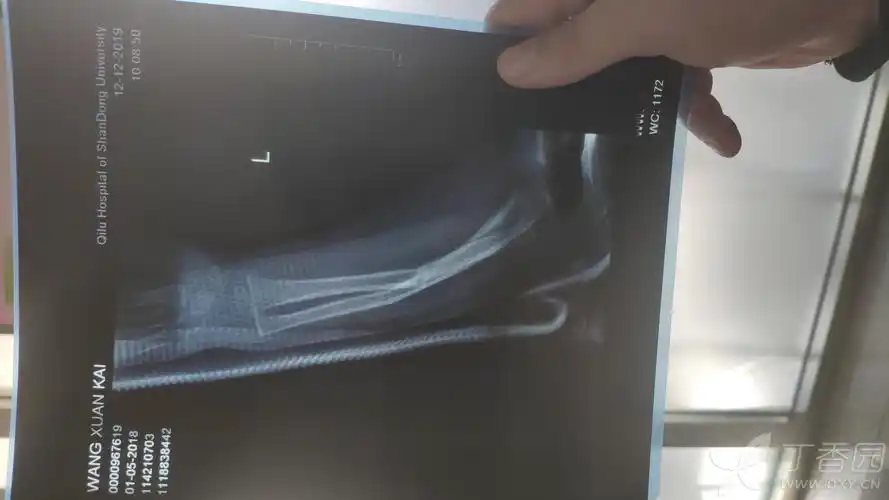

19个月手臂骨折 [病例帖]

在 x 线上看到的手臂粉碎性骨折照片